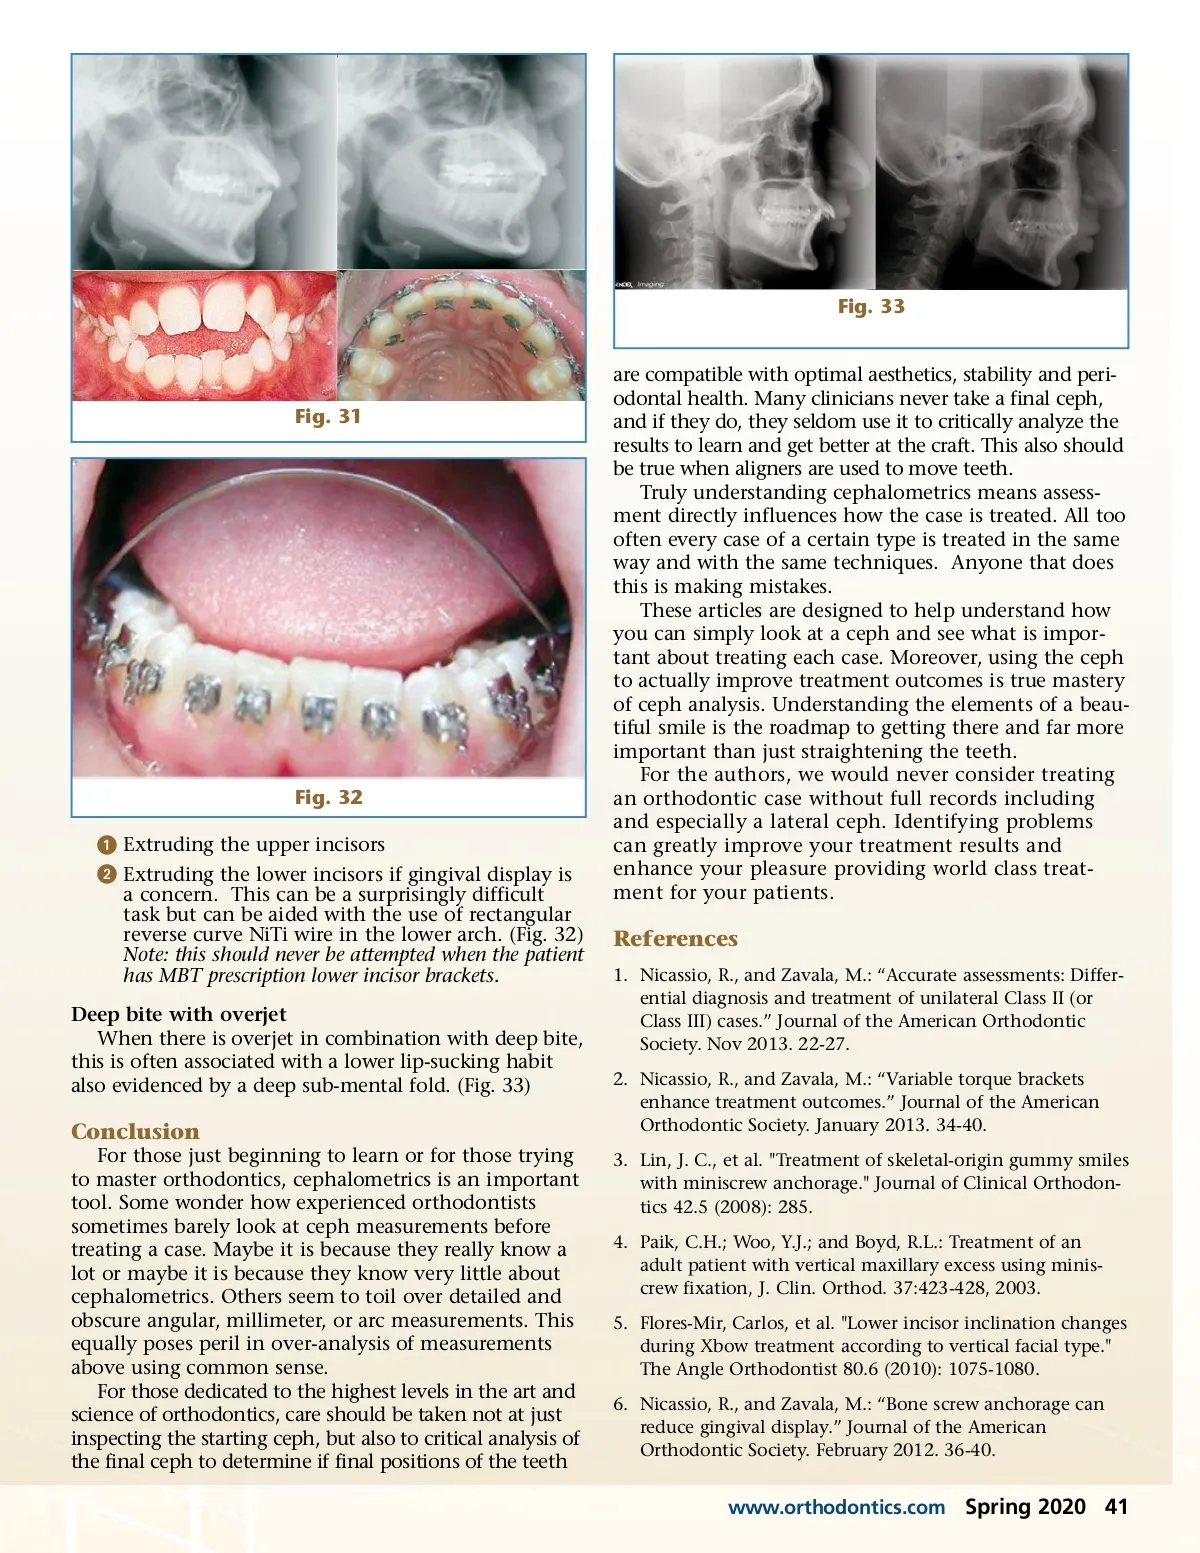

Fig. 29 Fig. 27 Fig. 30 lower incisors is on the lingual. Excessive lower incisor inclination can result in recession and tissue stripping lingually and this is seldom evaluated. (Fig. 26) It should also be noted that some of this excessive proclination problem can be mitigated with the use of lower incisor brackets with an MBT prescription (more negative torque) coupled with full sized rectangular wire, for 4-6 months. Note the bone labial to the lower incisors generated by using the light forces of rectangu-lar NiTi wire coupled with a maximally negative prescription lower incisor bracket. This enables bodily advancement without excessive proclination. (Fig. 27) Fig. 28 Lower incisors will further procline in non-extrac-tion cases as a result of: ᕡ Aligning crowded teeth ᕢ Leveling the curve-of-Spee ᕣ Administering Class II elastics As clinicians, we must be sensitive to how much the lower incisors advance. Excessive lower incisor procli-nation risks stability and periodontal health problems. (Fig. 22) Patients with thick attached gingiva are thought to best tolerate the advancement of lower anterior teeth. In fact, should a patient lack an adequate band of attached gingiva they should receive a graft before the ortho treatment commences in that arch. (Fig. 23) This case show an example of sliding pedicle graft that was performed. (Fig. 24) In the following case a cuspid was lost as it was advanced beyond the labial bone. (Fig. 25) But it is also important to evaluate what the proclination of the Worth Your Attention When Looking at a Ceph Deep Bite Deep bite is most often a symptom of dental Class II. But care should be taken on how to correct this. (Fig. 28) Deep bite can be corrected either by: ᕡ Supererupting the posterior teeth. This can be aided with incisal positioning of the upper and lower incisor brackets relative to the posterior teeth and/or with bite turbos. (Fig. 29) ᕢ Intruding the incisors if gingival display is a concern. In the mixed dentition this can be accomplished with upper utility arches. After full eruption this is best done using bone screw anchorage. 6 (Fig. 30) Open bite Open bite always means there is an anterior tongue thrust. These patients do not swallow properly with their elevator musculature. Instead, they swallow primarily with their tongue and their lips. Habit correc-tion with lingual cleats is essential to close an open bite. (Fig. 31) Open bite can be corrected either by: 40 Spring 2020 JAOS